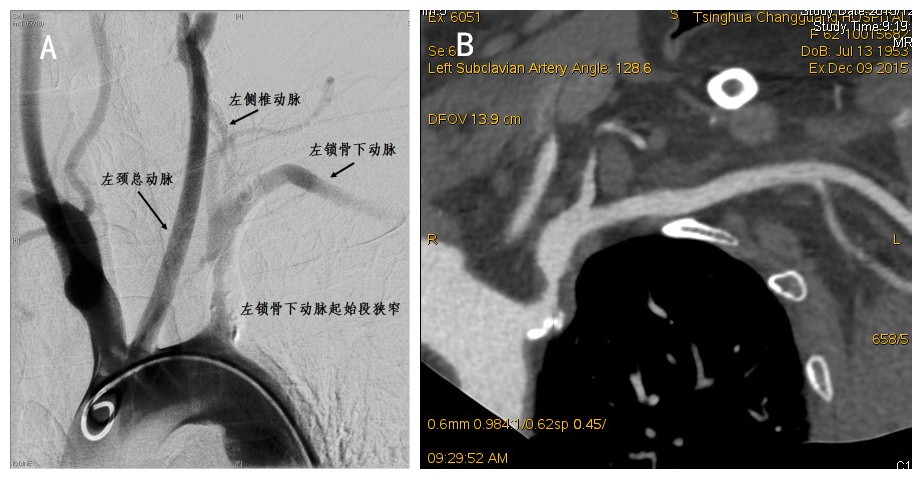

图1 动脉血管造影(A)及CTA血管重建(B)均可见患者左侧锁骨下动脉起始段明显狭窄